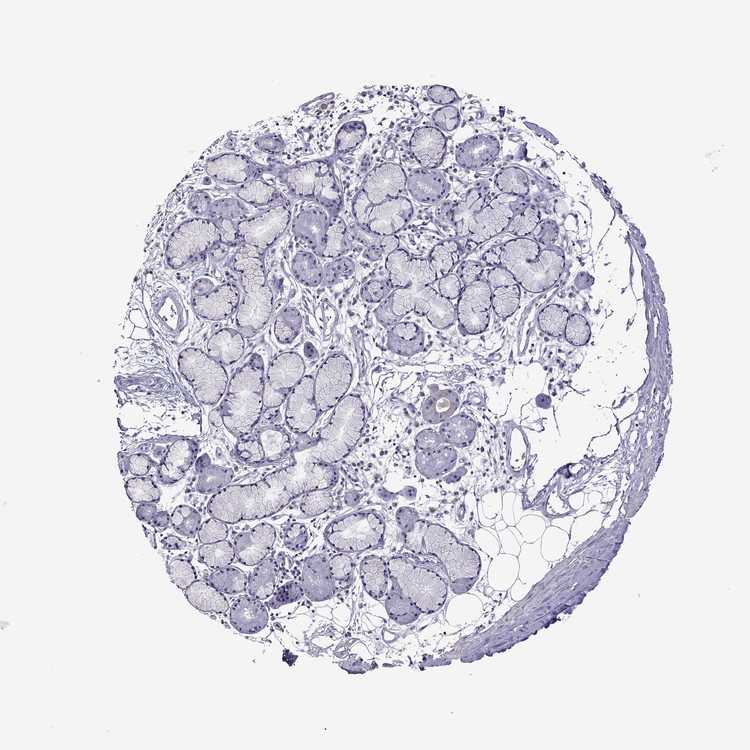

SOFT TISSUE 2 - Antibody stainingi

Antibody staining in the annotated cell types in the current human tissue is reported as not detected, low, medium, or high, based on conventional immunohistochemistry profiling in selected tissues. This score is based on the combination of the staining intensity and fraction of stained cells.

Each image is clickable and will lead to virtual microscopy that enables deeper exploration of all samples and also displays staining intensity scores, fraction scores and subcellular localization as well as patient and tissue information for each sample.

Antibody HPA007042Antibody HPA030048Antibody CAB022682

Fibroblasts Not detectedNot detectedNot detected

Peripheral nerve Not detectedNot detectedNot detected